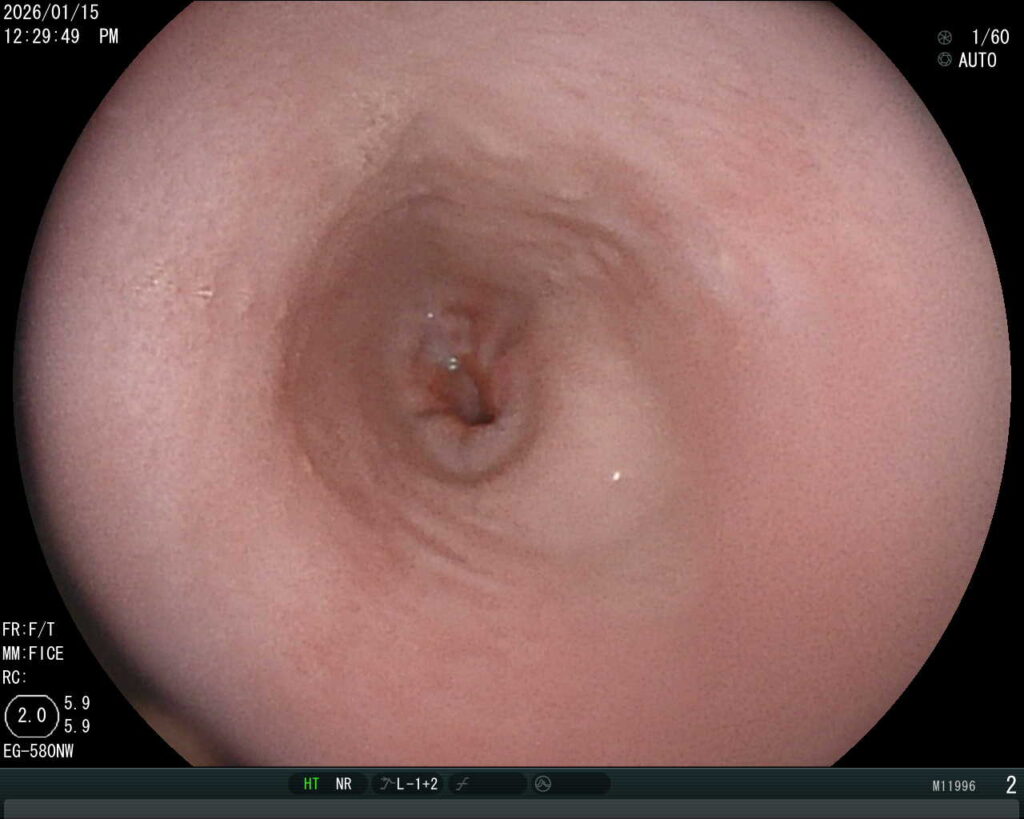

画像は胃の入口の噴門と胃内にある髪ゴムです。